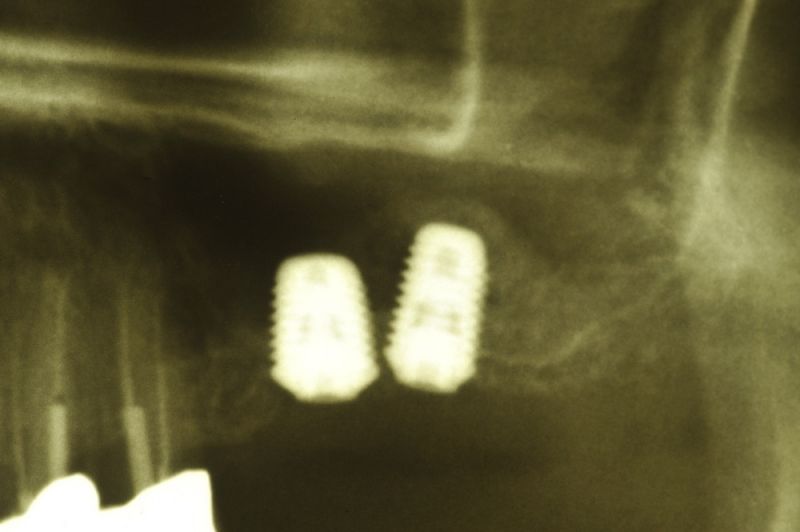

Am heutigen Tag sind in regio 26 und 27 zwei Implantate mit einem externen Sinuslift versorgt worden. Die Besonderheit des Eingriffs liegt darin, dass im Oberkieferseitenzahnbereich, bei einer noch vorhandenen Restknochenhöhe von wenigen Millimetern, zwei Implantate gesetzt und gleichzeitig eine Aufdoppelung des vorhandenen Restknochenangebots, durch die Schaffung eines Raumes zwischen knöcherner Abgrenzung der Kieferhöhle und der in die Kieferhöhle hinein verdrängten Kieferhöhlenmembran geschaffen werden konnte.

Nun wird die Membran vorsichtig in das eröffnete Ei hinein gedrückt. In die Eierschale wird an anderer Stelle, aber in der Nähe, nun ein zweites Loch gebohrt und in dieses Loch dann vorsichtig das Implantat hineingeschraubt. Das Implantat muss hierbei fest sitzen, oder wie man sagt: primärstabil! Ein Teil des Implantates ragt nun in das leere Ei hinein und zwar so, dass die verdrängte Membran des Eies sich wie eine Art Zirkuszelt über das Implantat hinweg spannt.

Der Raum, der nun zwischen dem Boden des Zirkuszelts und der Zirkuszeltspitze entsteht, der Mast, der das Zirkuszelt in der Mitte trägt, entsprich hier dem Implantat, wird nachfolgend mit einem Gemisch aus Knochen, Blut und Knochenersatzmaterialien aufgefüllt.

Genau das kann man dann auf dem Röntgenbild erkennen. So bildet sich innerhalb der Kieferhöhle, aber begrenzt durch die Kieferhöhlenmembran, neuer Knochen, der dann nachfolgend dem Implantat den knöchernen Halt gibt, den es unter späterer Belastung durch Kaudruck benötigt.

Wenn man so will, ermöglicht das Implantat, das wie ein Mittelmast das Zirkuszelt in die Höhe drückt, erst die Möglichkeit, dass der Hohlraum, der dann zwischen dem Zirkuszeltboden und der Mastspitze entsteht, sich nachfolgend mit Knochen auffüllt, so dass das Implantat am Ende des Einheilungsprozesses in voller Länge in neu gebildetem Knochen steht!

Das Problem der Operation besteht darin, dass zum einen noch genügend Restknochen vorhanden sein muss, damit das Implantat primärfest verschraubt werden kann, und zum anderen die Membran beim Ablösen von der Innenseite der Kieferhöhle, ähnlich wie bei der Mobilisierung der Eierhaut von der Innenseite der Eierschale, nicht zerreißt. Soll heißen, wenn es nicht gelingt den mittleren Zirkusmast sicher im Boden zu verankern, gelingt es auch nicht das Zirkuszelt nach oben hin aufzuspannen und damit den Hohlraum zu schaffen, in dem sich nachfolgend dann über mehrere Monate hinweg der Knochen bilden soll, der dem Implantat nachfolgend dauerhaft Halt verschafft.